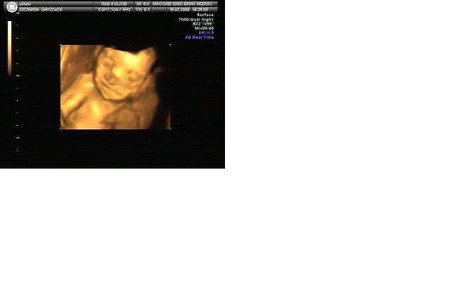

Вчера была на 3-м в жизни ультразвуке, наконец вытащила мужа полюбоваться на чадо - пусть начинает принимать участие в воспитании)))))))

На это раз обследование было очень подробным - головка, сердечко, все важные органы...Я лежала, как на иголках - так не терпелось пол узнать!

Направил луч на ладошки! Крошечные ладошки с пальчиками соприкасались и разжимались!

Говорит: видите, это аплодисменты!

И добавил: ВЕСЕЛАЯ ДЕВОЧКА!